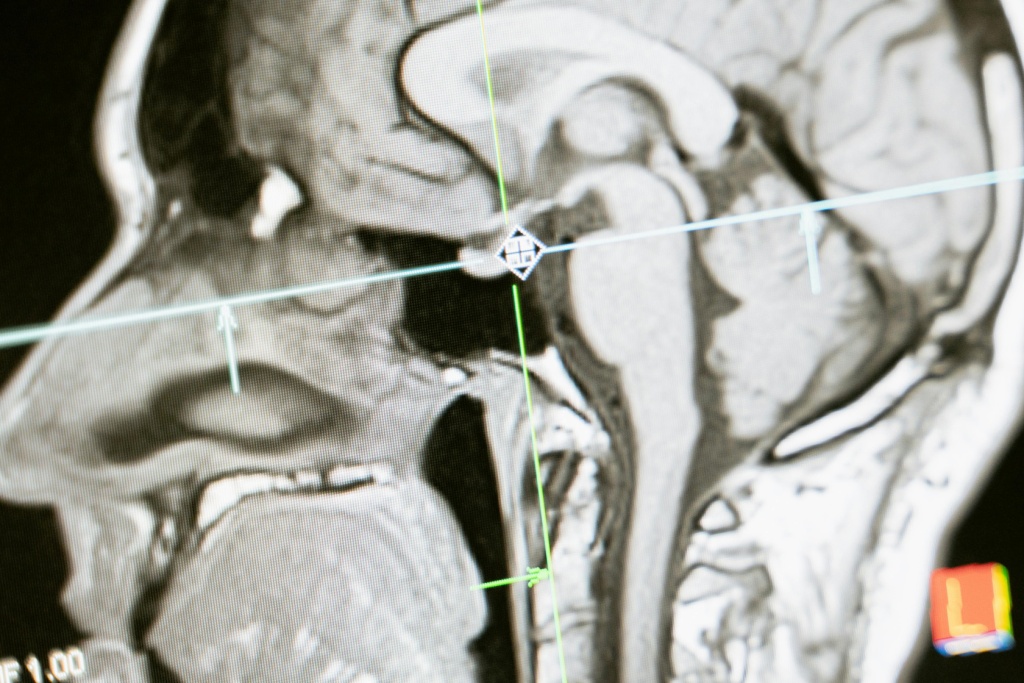

Магнитно-резонансная томография (МРТ) — это неинвазивный метод визуализации внутренних органов и тканей человеческого тела с высокой детализацией. Режимы МРТ представляют собой различные настройки оборудования, которые позволяют получать изображения с разной контрастностью и информативностью. Они определяются в зависимости от типа исследуемой ткани, целей исследования и необходимости выявления определенных патологий.

Изучение режимов магнитно-резонансной томографии (МРТ) является ключевым элементом в медицинской практике современных врачей. Это необходимо для точной диагностики различных заболеваний и патологий, а также для определения наиболее эффективных методов лечения. Понимание режимов МРТ позволяет врачам получить детальное представление о структуре и функционировании органов и тканей пациентов без необходимости проведения инвазивных процедур.

1 МРТ 1.jpg

Изучение режимов МРТ включает в себя основные принципы работы этого метода, понимание различных последовательностей импульсов и их влияния на получаемые изображения. Этот аспект особенно важен для тех областей медицины, где точная диагностика является ключевым моментом в определении стратегии лечения. Врачи, специализирующиеся в радиологии, нейрологии, онкологии, ортопедии и других смежных областях, активно изучают и применяют знания о режимах МРТ в своей практике.

Понимание режимов МРТ позволяет врачам точнее определять характер заболеваний, выявлять патологии на ранних стадиях и мониторить динамику их развития. Это значительно улучшает прогноз лечения и позволяет выбирать наиболее подходящие методы терапии, что, в конечном итоге, способствует увеличению выживаемости и качества жизни пациентов.

Предположим, у пациента обнаружили подозрительные изменения в тканях мозга на рентгеновских снимках. Для более точной диагностики врач назначает ему МРТ. Благодаря пониманию режимов МРТ, радиолог способен выбрать оптимальные параметры сканирования, что позволит получить высококачественные изображения мозговых структур с высоким разрешением. Это поможет точно определить характер и стадию заболевания и разработать наиболее эффективный план лечения для пациента.

Статистика подтверждает значимость изучения режимов МРТ: по данным американской ассоциации радиологов, более 75% всех диагностических решений в медицине принимаются на основе результатов МРТ, что подчеркивает важность этого метода для современной клинической практики.

Изучение режимов МРТ – это важный шаг на пути к повышению качества диагностики и лечения пациентов. Знание особенностей каждого режима позволяет врачу выбрать оптимальный вариант исследования, правильно интерпретировать полученные изображения и назначить наиболее эффективную терапию.